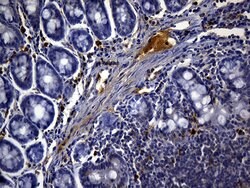

CD3 epsilon is part of the CD3 subunit complex which is crucial in transducing antigen-recognition signals into the cytoplasm of T cells and in regulating the cell surface expression of the TCR complex. T cell activation through the antigen receptor (TCR) involves the cytoplasmic tails of the CD3 subunits CD3 gamma, CD3 delta, CD3 epsilon and CD3 zeta. These CD3 subunits are structurally related members of the immunoglobulins super family encoded by closely linked genes on human chromosome 11. The CD3 components have long cytoplasmic tails that associate with cytoplasmic signal transduction molecules and this association is mediated at least in part by a double tyrosine-based motif present in a single copy in the CD3 subunits. CD3 may play a role in TCR-induced growth arrest, cell survival and proliferation. The CD3 antigen is present on 68-82% of normal peripheral blood lymphocytes, 65-85% of thymocytes and Purkinje cells in the cerebellum. It is never expressed on B or NK cells. Decreased percentages of T lymphocytes may be observed in some autoimmune diseases. The genes encoding the CD3 epsilon, gamma and delta polypeptides are located on chromosome 11. Defects in this gene are associated with T cell immunodeficiency and has been linked to Type 1 Diabetes deficiency in women.Specifications

| Immunocytochemistry, Immunofluorescence, Immunohistochemistry (Paraffin) | |